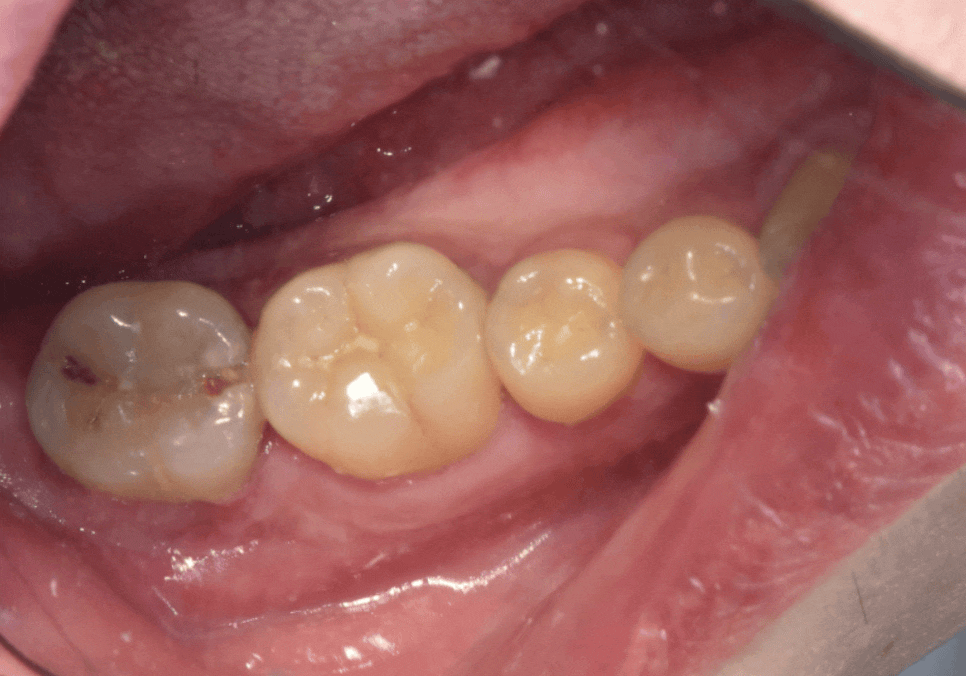

250409

덕분에 큰 문제없이

지르코니아 보철로 마무리가 잘 되었네요~

240527(전) 250409(후)